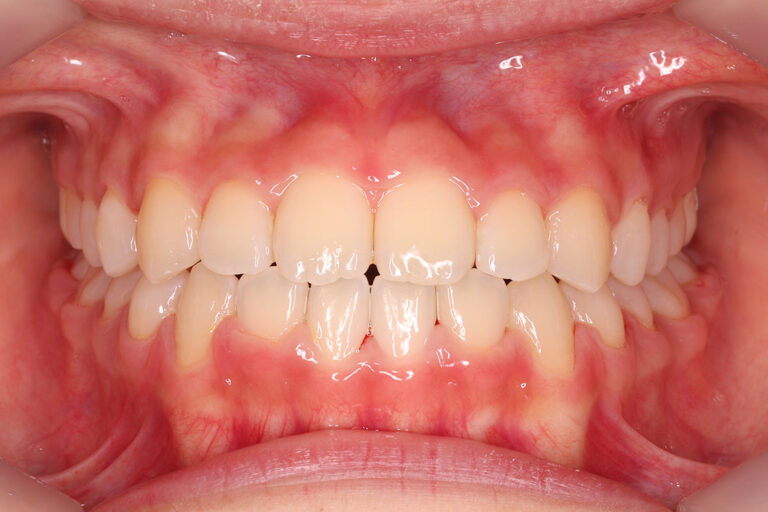

| 小児矯正から始められた受け口傾向の患者さんです。

前歯が反対咬合で、永久歯の萌出スペース不足による上顎前歯部の叢生(がたつき)が予測できる患者さん。 骨格的に、上顎と比べ下顎が大きく、成長によっては外科手術になる可能性もありましたが、 外科手術はせず、矯正治療のみで咬み合わせを改善しています。 小児矯正で、前歯部の被蓋(重なり)の改善まで治療を行い、下顎の成長を観察した後に、 永久歯列から、マルチブラケット装置により非抜歯にて配列しました。 来院間隔1.5カ月でしたが、平均より短く治療を終えることが出来ました。 マルチブラケット 動的治療期間 2年1か月 調整回数14回